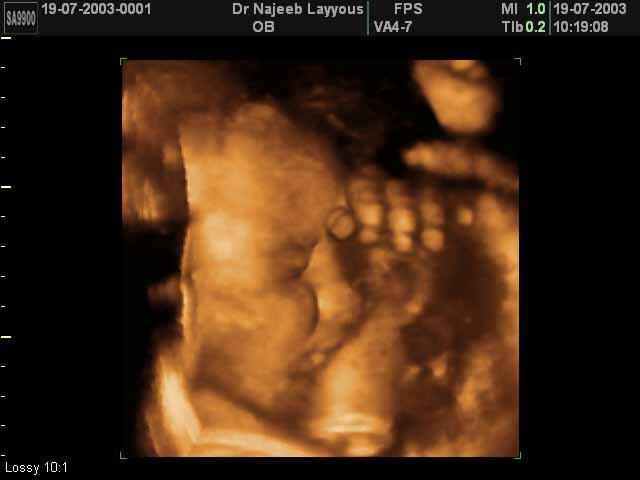

- 3D Fetal Profile Ultrasound Scan Photos

3D Fetal Profile Ultrasound Scan Photos | Dr N Layyous